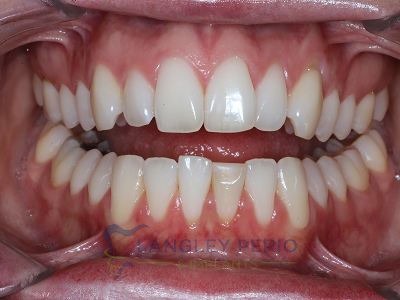

Case 3

Alloderm tissue grafting performed to improve root coverage and esthetics. This technique does not require tissue to be taken from the patient’s palate.